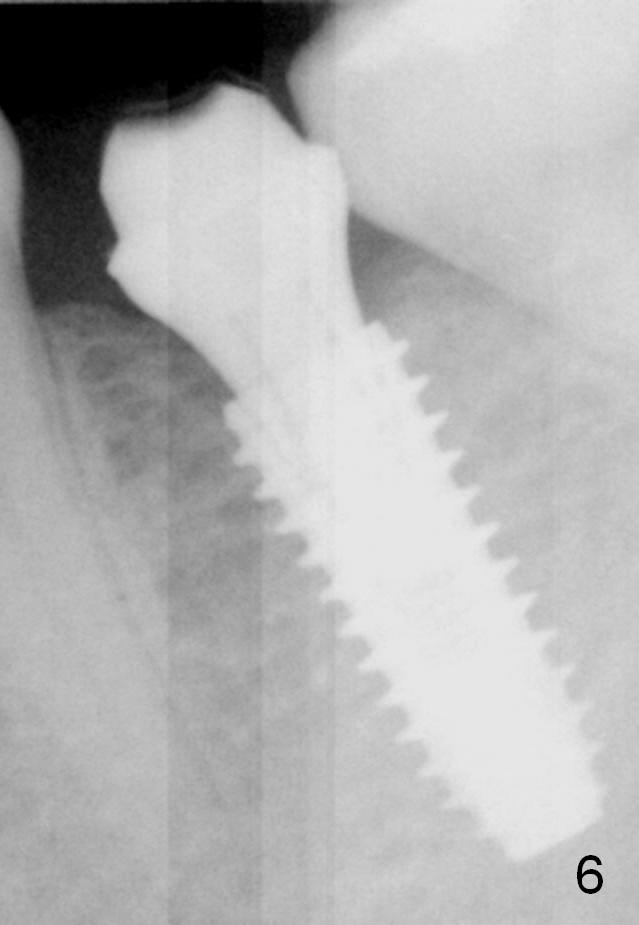

There is no bone loss 3 months postop (Fig.6). Mesial laser gingivectomy and lingual margin prep are conducted prior to impression.